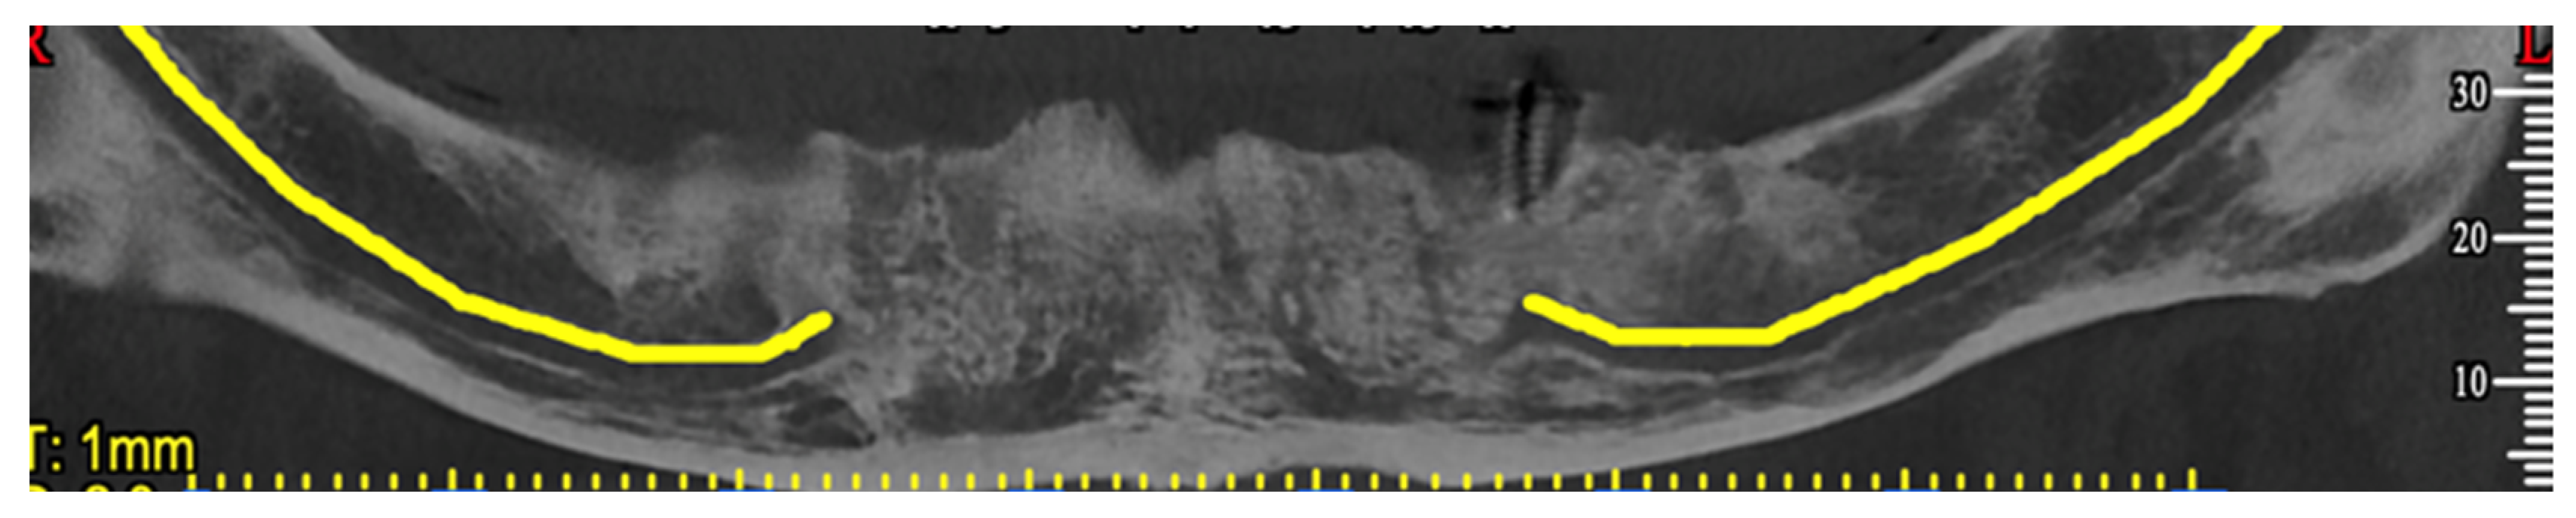

2. Case Report

3. Surgical Strategy